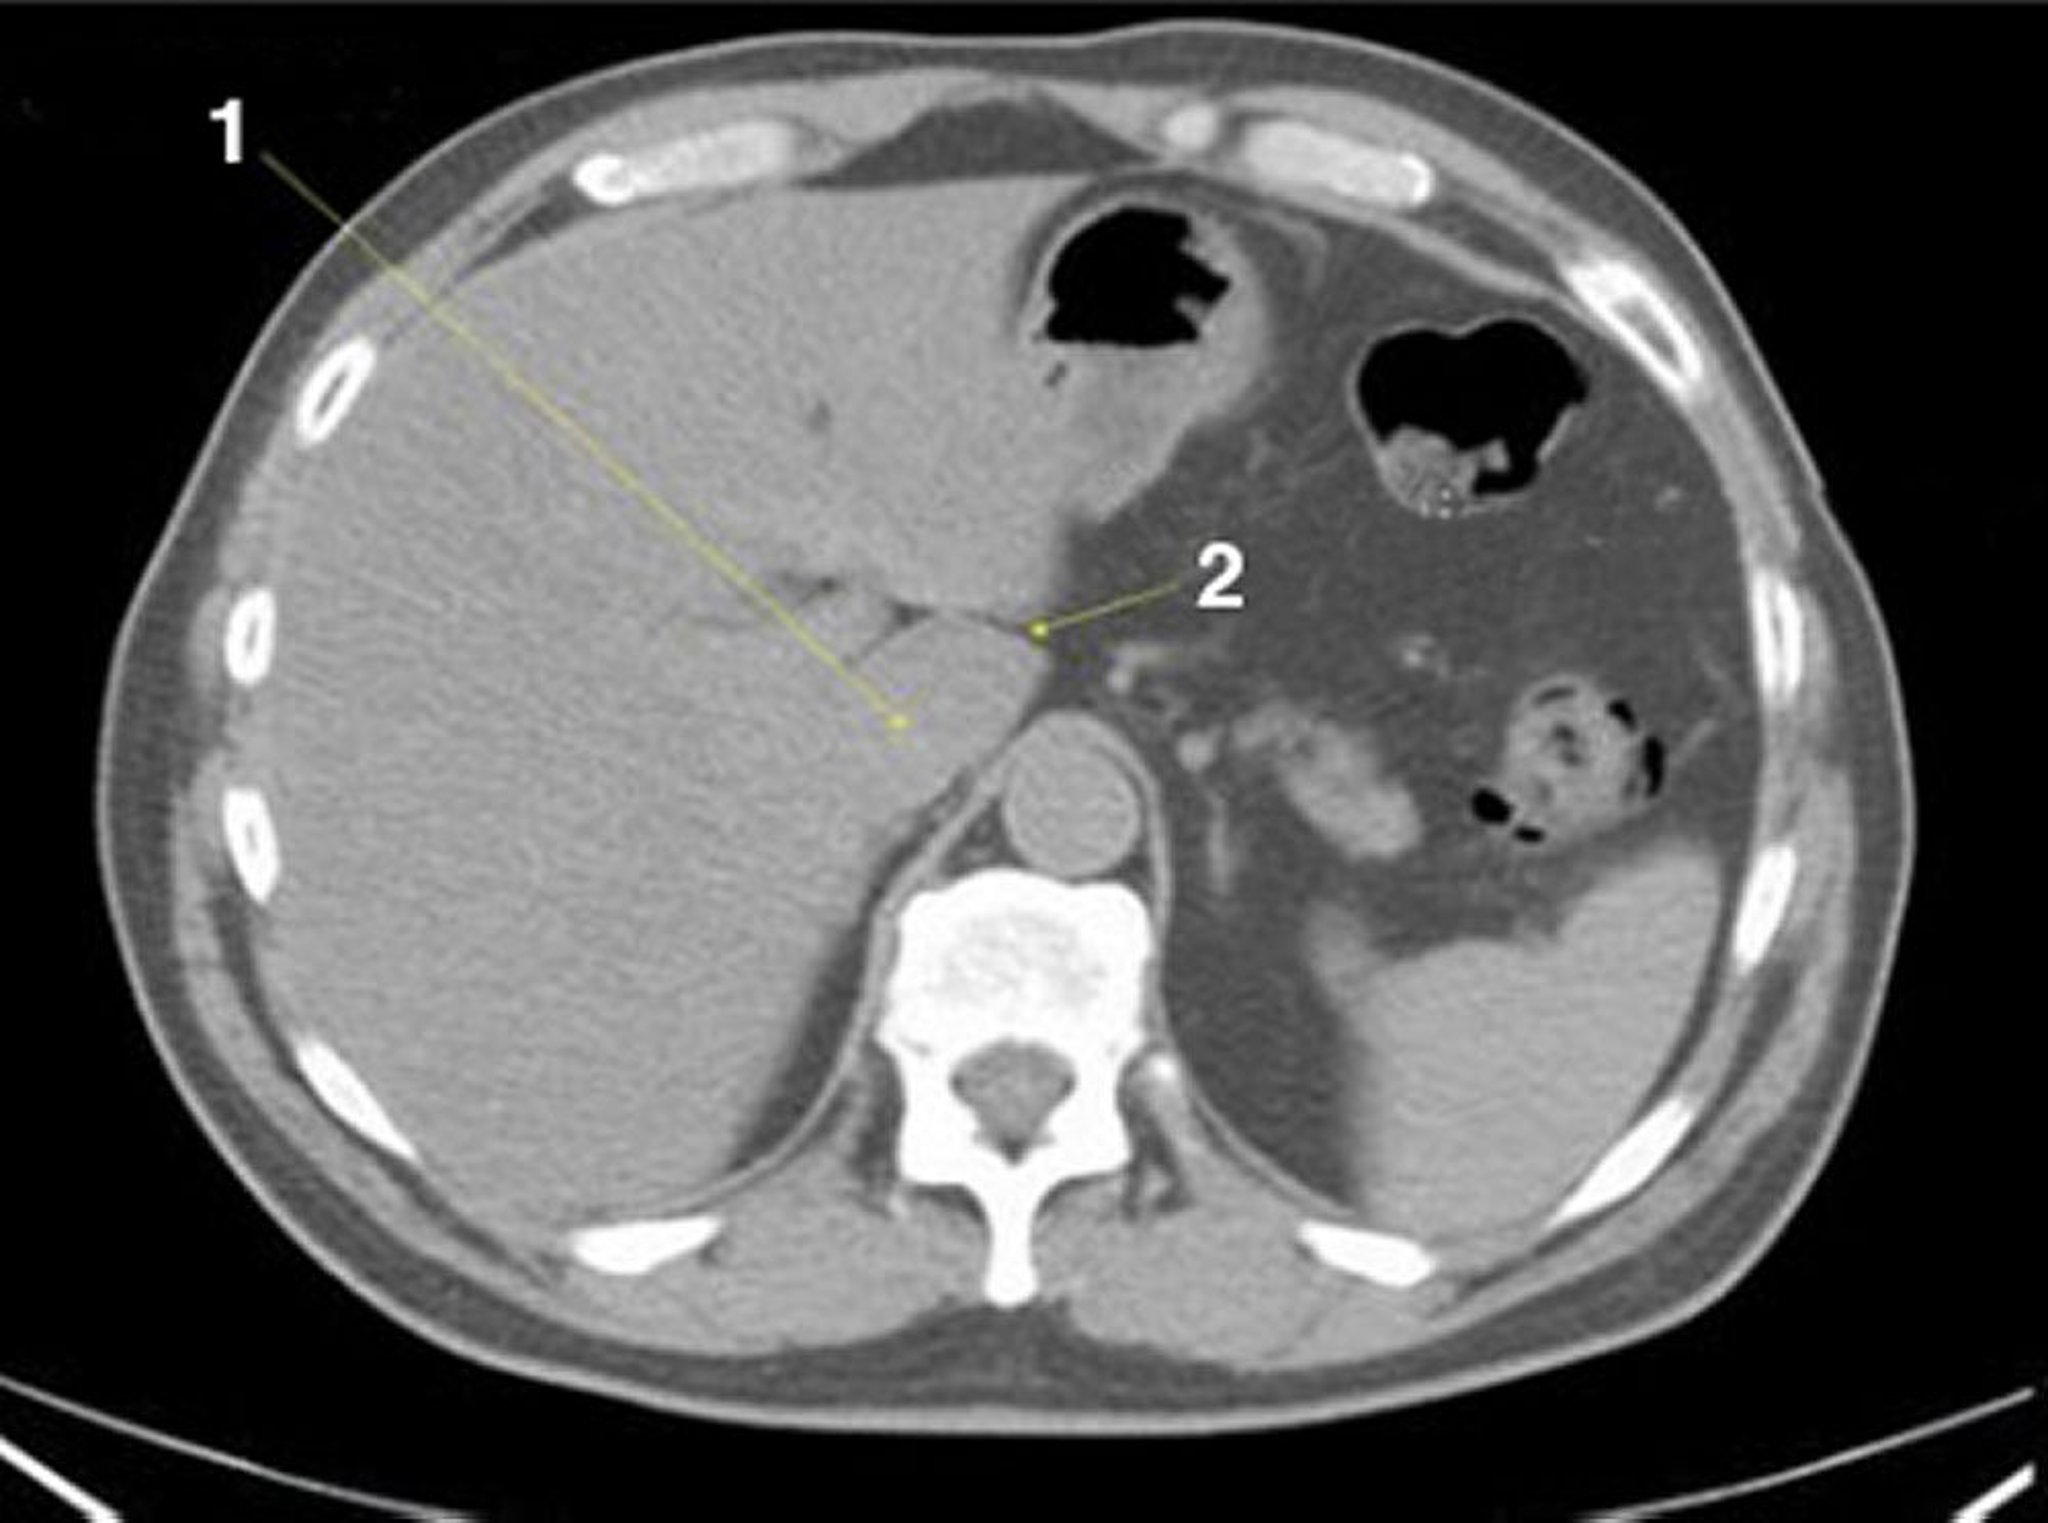

Noncontrast CT Scan of the Abdomen and Pelvis Showing Normal Anatomy (Slide 4)

1 = caudate lobe of liver; 2 = fissure for ligamentum venosum.